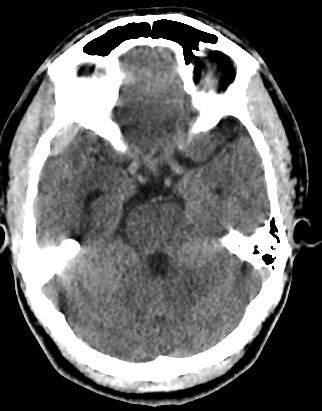

brain CT scan

A brain CT scan, also known as a computed tomography scan or CAT scan, is a non-invasive imaging procedure that uses X-rays to create detailed cross-sectional images of the brain and surrounding structures. It's a common diagnostic tool for evaluating head injuries, strokes, brain tumors, and other neurological conditions. Here's a more detailed explanation: What it is: A brain CT scan uses a series of X-ray beams that rotate around the head, capturing multiple images from different angles. These images are then processed by a computer to create detailed cross-sectional views of the brain, allowing doctors to visualize the brain's structures and identify any abnormalities. The scan can be performed with or without contrast dye, which helps to highlight certain tissues and blood vessels for better visualization. Why it's used: Traumatic brain injuries: CT scans are often the first imaging test used to assess the extent of head injuries and identify potential fractures, bleeding, or swelling. Stroke: CT scans can quickly identify whether a stroke is caused by a blood clot (ischemic stroke) or bleeding (hemorrhagic stroke), guiding appropriate treatment. Brain tumors: CT scans can help detect and assess the size and location of brain tumors. Other neurological conditions: CT scans can also be used to diagnose conditions like hydrocephalus (excess fluid in the brain), aneurysms (bulges in blood vessels), and certain types of dementia. Guiding procedures: CT scans can be used to guide biopsies or other procedures involving the brain. What to expect during the procedure: You will lie on a table that slides into the CT scanner, which is a large, doughnut-shaped machine. The scan itself is painless, but some people may experience slight discomfort from lying still on the hard table. If contrast is used, you may feel a warm or flushing sensation, or a metallic taste in your mouth. The scan typically takes only a few minutes. Risks and Precautions: CT scans involve exposure to radiation, but the risk from a single scan is generally considered low. If you are pregnant, it's important to inform your doctor, as alternative imaging methods may be considered to avoid exposing the fetus to radiation. If you have any allergies, particularly to contrast dye, make sure to inform your doctor.